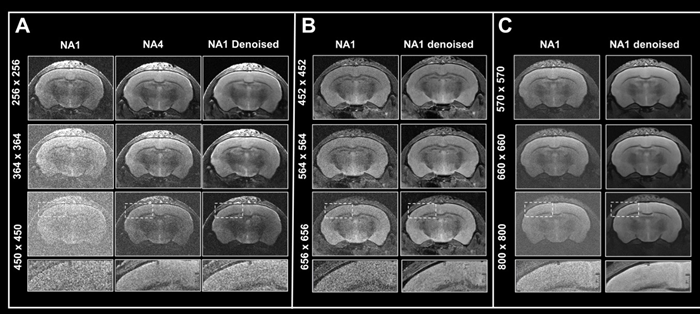

This article shows how Smart Noise Reduction may be utilized to reduce acquisition times while retaining image quality.

Boosting resolution

Figure 6. Boosting resolution. Ex vivo T2-weighted TurboRARE data of a fixed mouse head acquired at A) 3 Tesla, B) 7 Tesla, and C) 9.4 Tesla. All images were acquired with 0.8 mm (A) and 0.7 mm (B, C) slice thickness and with a field-of-view of 20 x 20 mm2 and the given matrix size using either no averaging or acquiring 4 averages. Images were reconstructed with no denoising (NA1 and NA4), or after denoising (NA1 Denoised) using a network Large, applying a pre-denoising level of 50 % and denoising level of 70 %. Image Credit: Bruker BioSpin Group

In Fig 6, axial T2-weighted TurboRARE images of a fixed mouse head taken at various field strengths are compared. Images were obtained with a fixed field-of-view of 20 x 20 mm2, slices that were 0.8 mm (3 Tesla) and 0.7 mm (7 and 9.4 Tesla) thick, and changing matrix sizes to produce images with various spatial resolution.

For images acquired at 3, 7, and 9.4 Tesla, the matrix sizes were raised by up to 1.8, 2.6, and 3.1 (compared to the reference protocols' matrix size of 256). These resolution upgrades cause a reduction in SNR for each image.

The loss in SNR can be accounted for by averaging, therefore extra data was collected using four averages.

A comparison of non-denoised averaged images and single averaged images that were denoised demonstrates that denoising reduces increased image noise at higher resolutions and produces images of comparable quality to those generated through averaging.

The advantages in image quality from denoising are greater with data recorded at 3 Tesla, when increasing resolution provides images that are more difficult to interpret, as opposed to data acquired at 7 and 9.4 Tesla, where SNR is naturally higher.

Nonetheless, images taken at 7 and 9.4 Tesla benefit significantly from denoising during reconstruction since the intrinsic higher SNR of these images may be used to pick smaller voxel sizes.

This shows that denoising allows for better resolutions within a given unit time by reducing the requirement for averaging. This can also be useful when averaging is neither desirable nor practical.